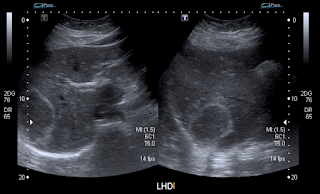

Dolor en hipocondrio derecho

Femenina de 31 años